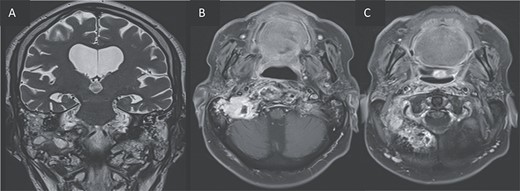

For better diagnostic assessment, the patient underwent a magnetic resonance imaging (MRI) (Figs 3 and 4), it showed the following findings:

An expansile cystic-necrotic lesion localized in the central region of the clivus, characterized by a hypointense rim on T2-weighted images.

Post-gadolinium T1-weighted imaging delineating the cystic center with thick peripheral rim enhancement.

Diffusion-weighted imaging (DWI) and apparent diffusion coefficient (ADC) maps demonstrating central restricted diffusion.

(A, B) Axial T2 and sagittal T1 images showing an expansile cystic lesion in the center of the clivus hyperintense in T2, hypointense in T1, with a rim hypointense in T2-weighted image. (C) Post-gadolinium T1-weighted shows a peripheral rim enhancement of the clival lesion.